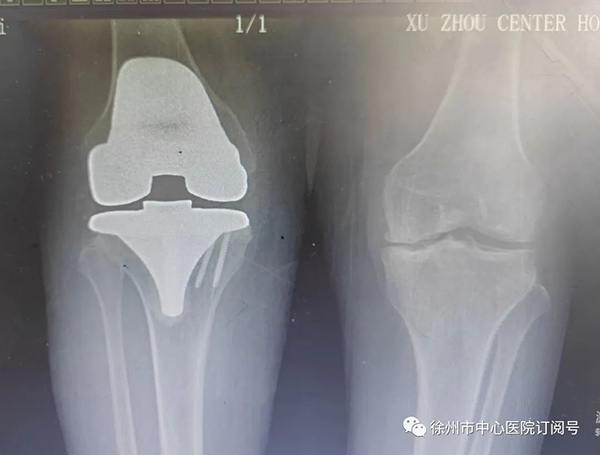

(手術(shù)前后影像對比)

術(shù)中,發(fā)現(xiàn)患者股骨、脛骨、髕骨軟骨廣泛剝脫,髕骨關(guān)節(jié)軟骨下骨裸露,邊緣有大量骨贅形成,內(nèi)外側(cè)半月板退變,邊緣毛糙,關(guān)節(jié)腔內(nèi)可見大量淡黃色滑液,滑膜增生肥厚。那鍵憑借豐富的臨床經(jīng)驗,將患者右膝關(guān)節(jié)全部置換,手術(shù)順利完成。

術(shù)后,潘女士的腿恢復了正常,完全和正常人一樣可以伸直、彎曲。術(shù)后幾天,便可下床走路。潘女士及家人對手術(shù)效果十分滿意,連連向那鍵道謝。